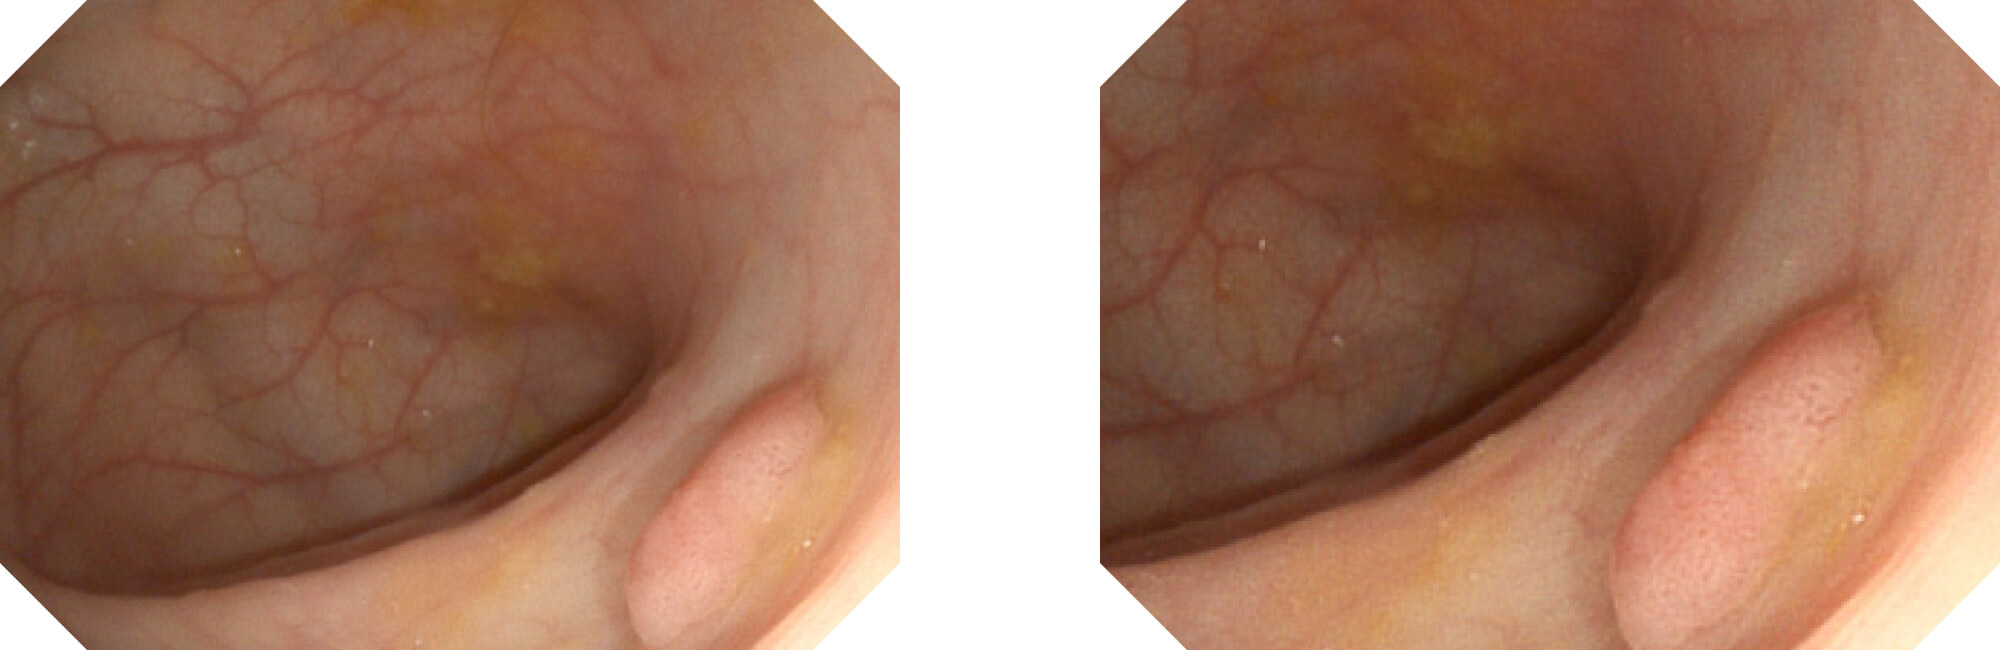

高清数字信号结合构造强调和色彩增强,多重图像处理技术能让每一个图像都清晰可见。

构造强调

色彩增强

电子放大